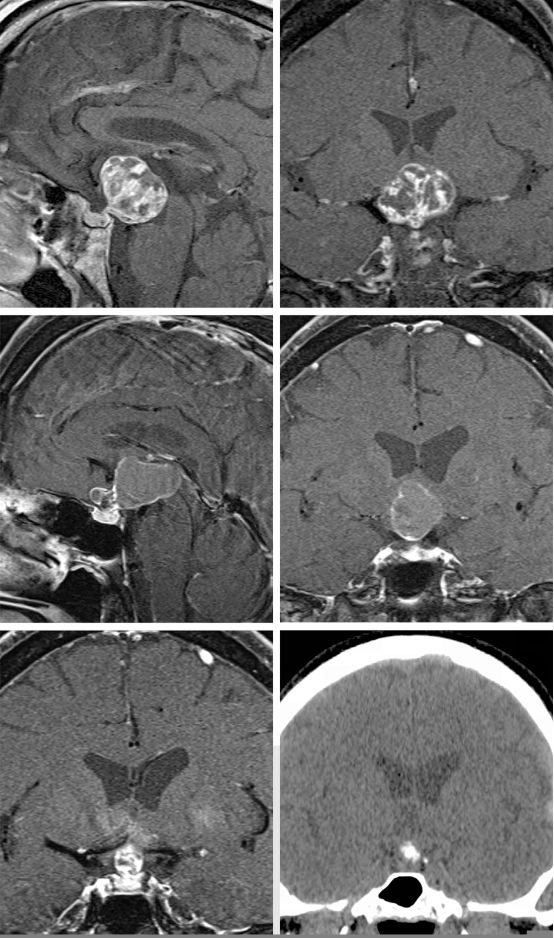

图1. 显示两个不同大小和形态的颅咽管瘤患者的影像。在上排的影像显示一个大的稍微实性的颅咽管瘤,能够经额下入路通过终板暴露。另一方面,在中排和低排的影像显示一个部分囊实性肿瘤,适合经鼻入路。注意右侧下面的影像为CT上发现的结节性钙化。两个肿瘤对垂体柄的明显包绕使得在切除过程中试图保留垂体柄几乎不可能。